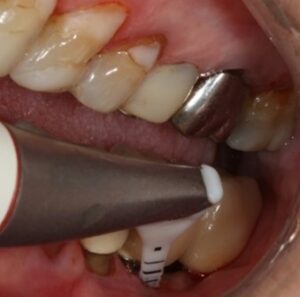

• un traitement comprenant un débridement mécanique, suivi d’un aéropolissage poudre d’air avec de la glycine (fig. 7), suivi d’un conditionnement d’acide citrique ou d’eau oxygénée à 10 volumes avec un rinçage vigoureux de la surface implantaire à l’eau stérile après chaque étape, serait capable de décontaminer la surface infectée. (Rosen et al 2018)

Figure 7: aéro polissage de la surface implantaire à l’aide d’une tête fine (Prophyflex Kavo), après élimination du tissu de granulation